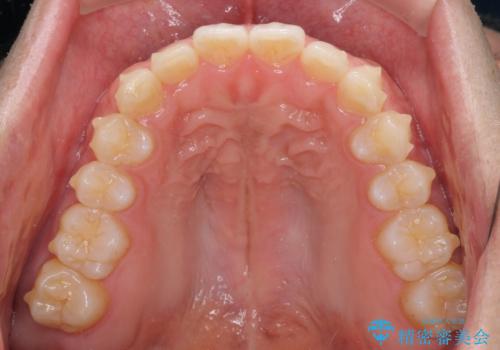

細かい隙間にものがはさまる インビザラインによる矯正治療

- 上下の前歯の隙間を気にして来院された患者様です。

インビザラインを用い、上下歯列のスペースを閉じていくこととしました。

銀行にお勤めのため、突然の転勤により通院が大変な状況となりましたが、インビザラインであれば2-3ヶ月に1度を目安に来院いただき、無事に治療を終えることができました。